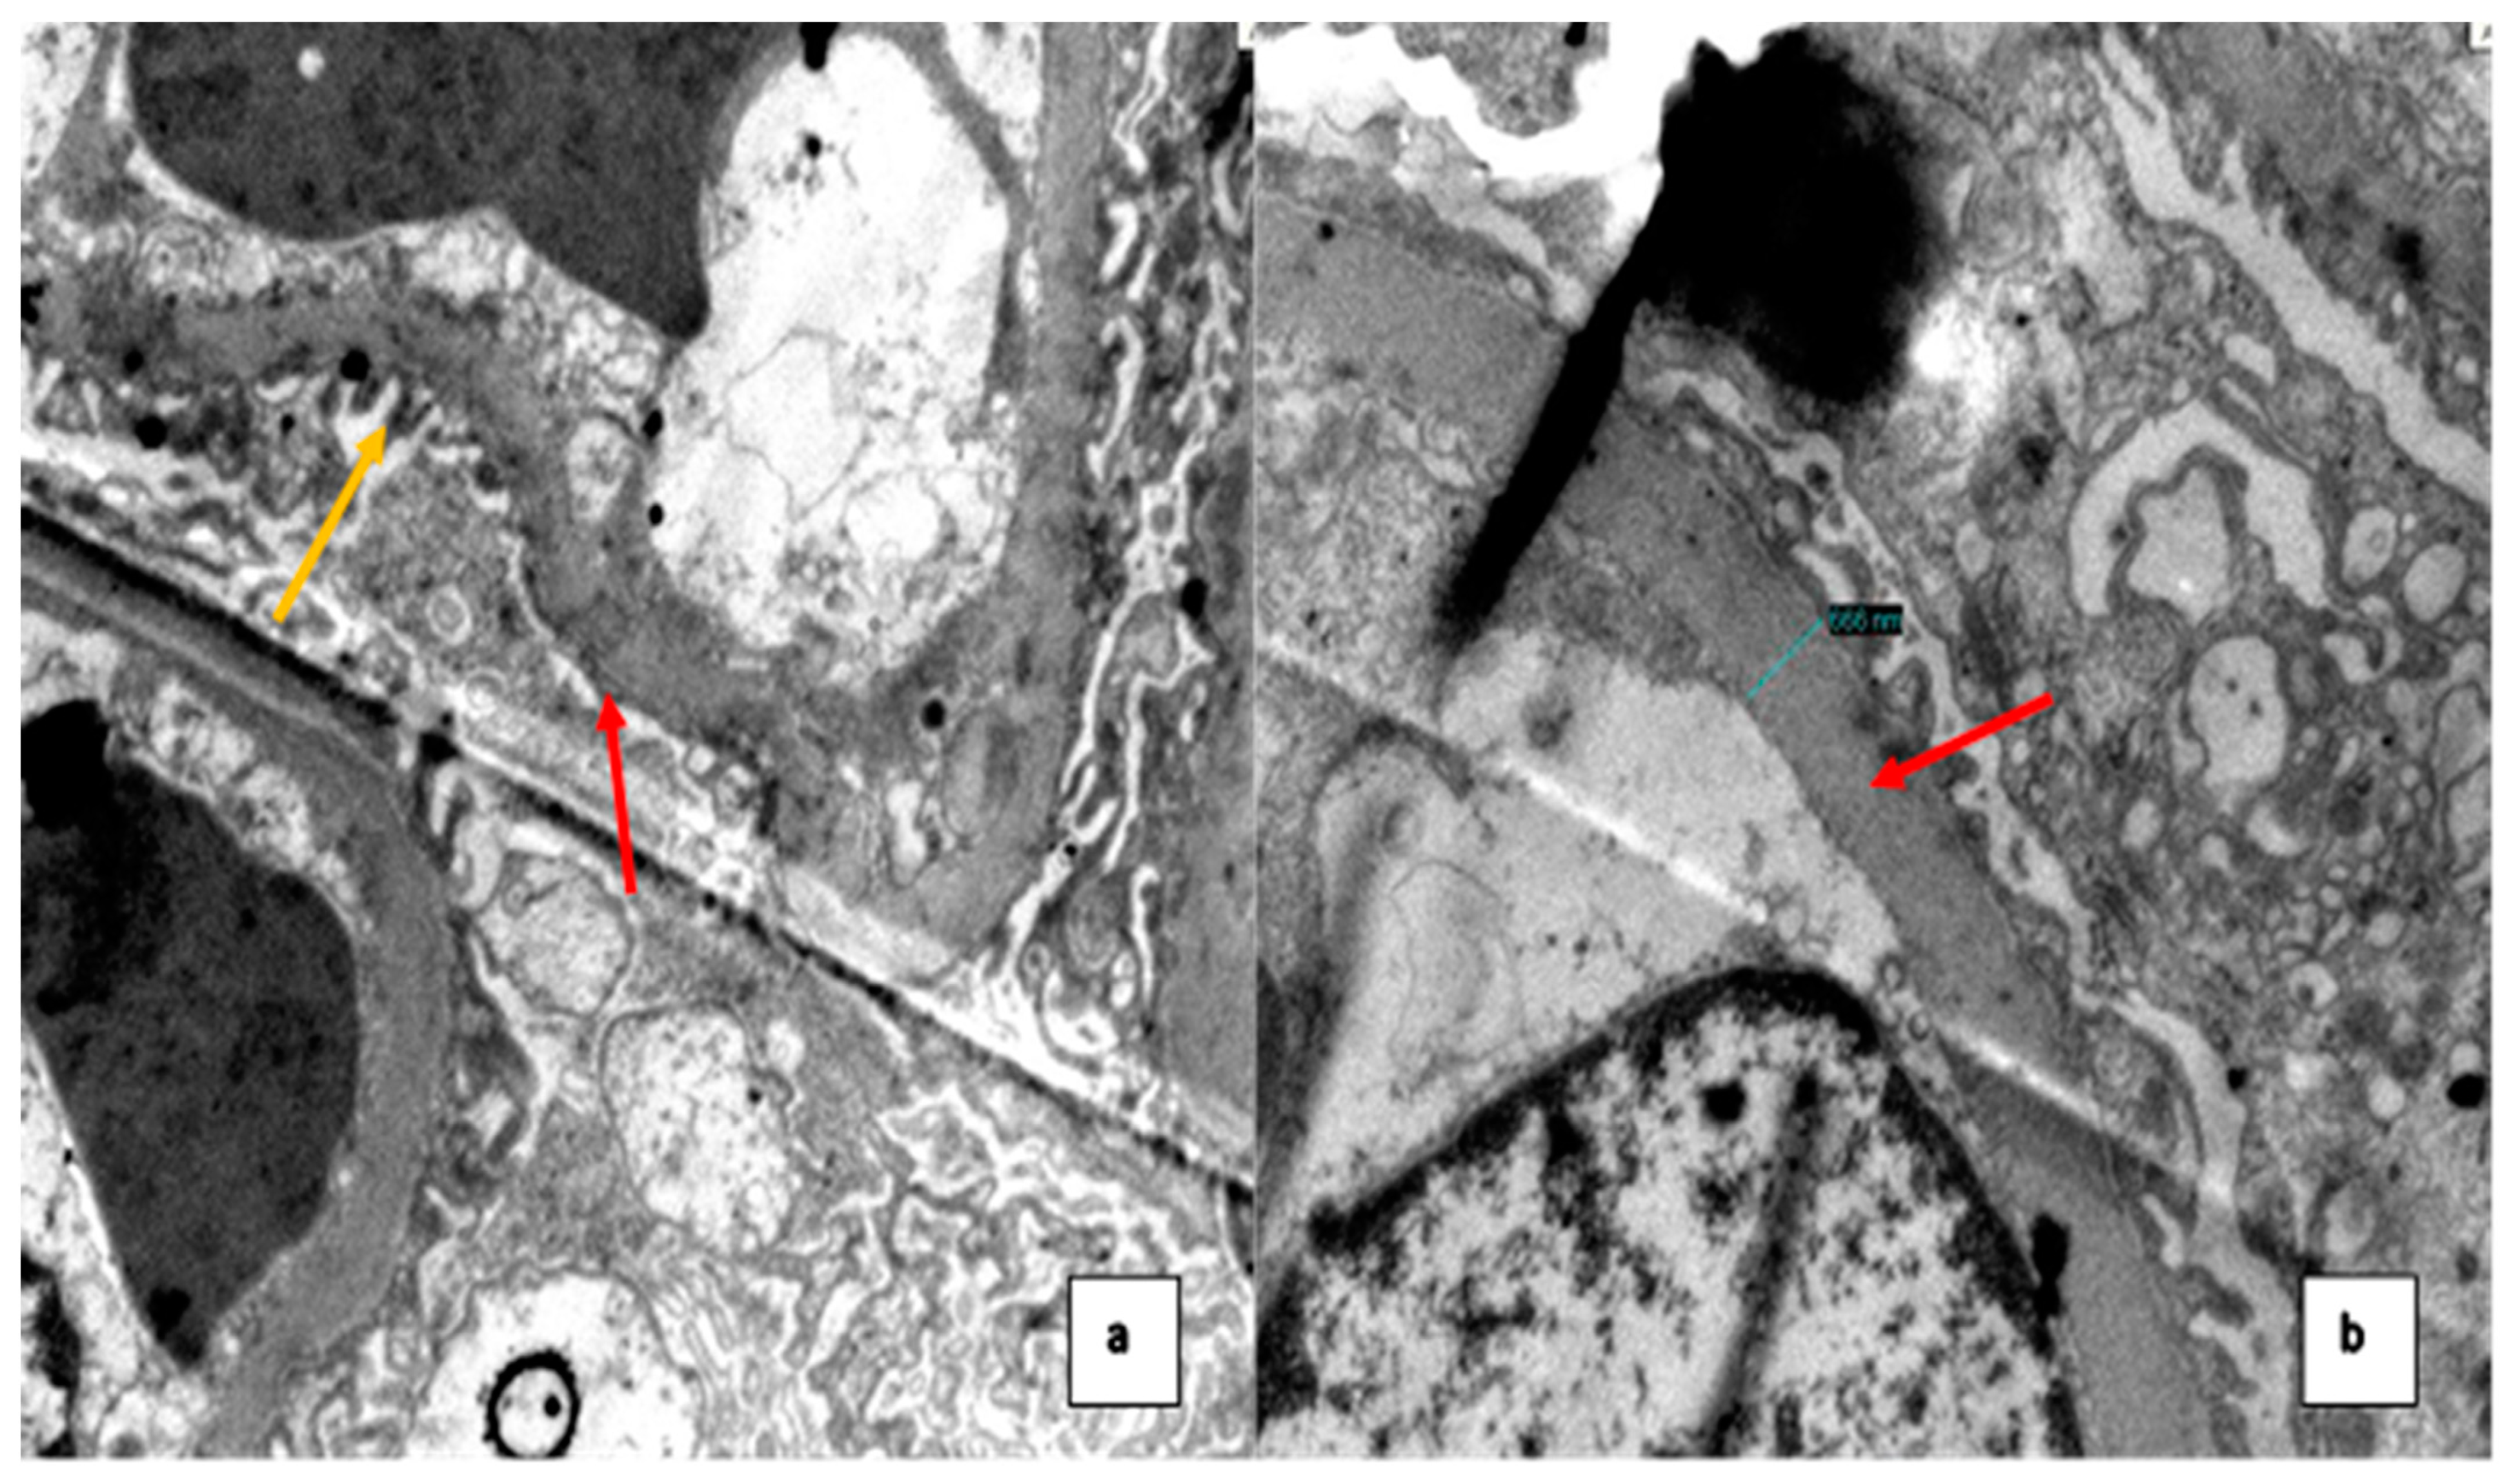

2. Case Presentation